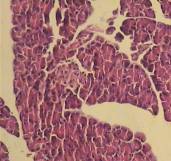

The morphometric examination of the normal pancreatic tissue sections showed that the islets are of normal size and have intact Beta cells. STZ-treated pancreatic specimens showed shrunk islets with degenerated Beta cells and peripheral lymphocytic infiltrate. Sections of pancreatic tissue treated with Pio (10 mg/kg) showed small islets with decreased number of Beta cells than control. Sections of pancreatic tissue treated with MP (500 mg/kg) showed that the islets had decreased number of Beta cells. Sections of pancreatic tissue treated with Pio (10 mg/kg) in combination with MP (250 mg/kg) showed atrophic islets with few Beta cells (fig. 10), (table 1).

Fig. 10: Photomicrograph of Pio, MP and Pio+MP on liver in STZ-treated diabetic rats. STZ: streptozocin Pio: pioglitazone, MP: Monascus purpureus. [mean±SEM, n= 6] significant, * when compared to normal and @ P<0.05 when compared to control diabetic

A-Section in control liver tissue showing preserved hepatic architecture with normal hepatocytes (H and E, X100). B-Section in normal pancreatic tissue, the islets show intact Beta cells (H and E, X100). C-Normal pancreatic tissue section with overlapped binary image showing a mean islet area 1278.26 square micrometer. D-Section of liver tissue from STZ treated rat showing normal hepatic architecture with focal inflammatory cell infiltrates with focal hepatocytic degeneration (H and E, X100). E-STZ pancreatic tissue section, the islets show degenerated Beta cells with peripheral lymphocytic infiltrate (H and E, X100). F-Pancreatic sections from STZ treated rat with overlapped binary image showing a mean islet area 785.42 square micrometer. J-Section of liver tissue from Pio treated rat showing moderate degeneration of hepatocytes with mild cellular infiltrate (H and E, X100). K-Pio treated pancreatic tissue section showed that the islets have few Beta cells (H and E, X100). L-Pancreatic sections from Pio treated rat with mean islet area 549.28 square micrometer. M-Section of liver tissue from Stat treated rat showing moderate hepatic infiltration by inflammatory cells (H and E, X100). N-Stat treated pancreatic tissue section showed that the islets had decreased number of Beta cells (H and E, X100). O-Pancreatic sections from Stat treated rat with mean islet area 724.11 square micrometer. P-Section of liver tissue from PS treated rat showing focal degeneration of hepatocytes (H and E, X100). Q-PS treated pancreatic tissue section; the islets show decreased number of Beta cells with peripheral inflammatory cellular infiltrate (H and E, X100). R-Pancreatic sections from PS treated rat with mean islet area 659.89 square micrometer.